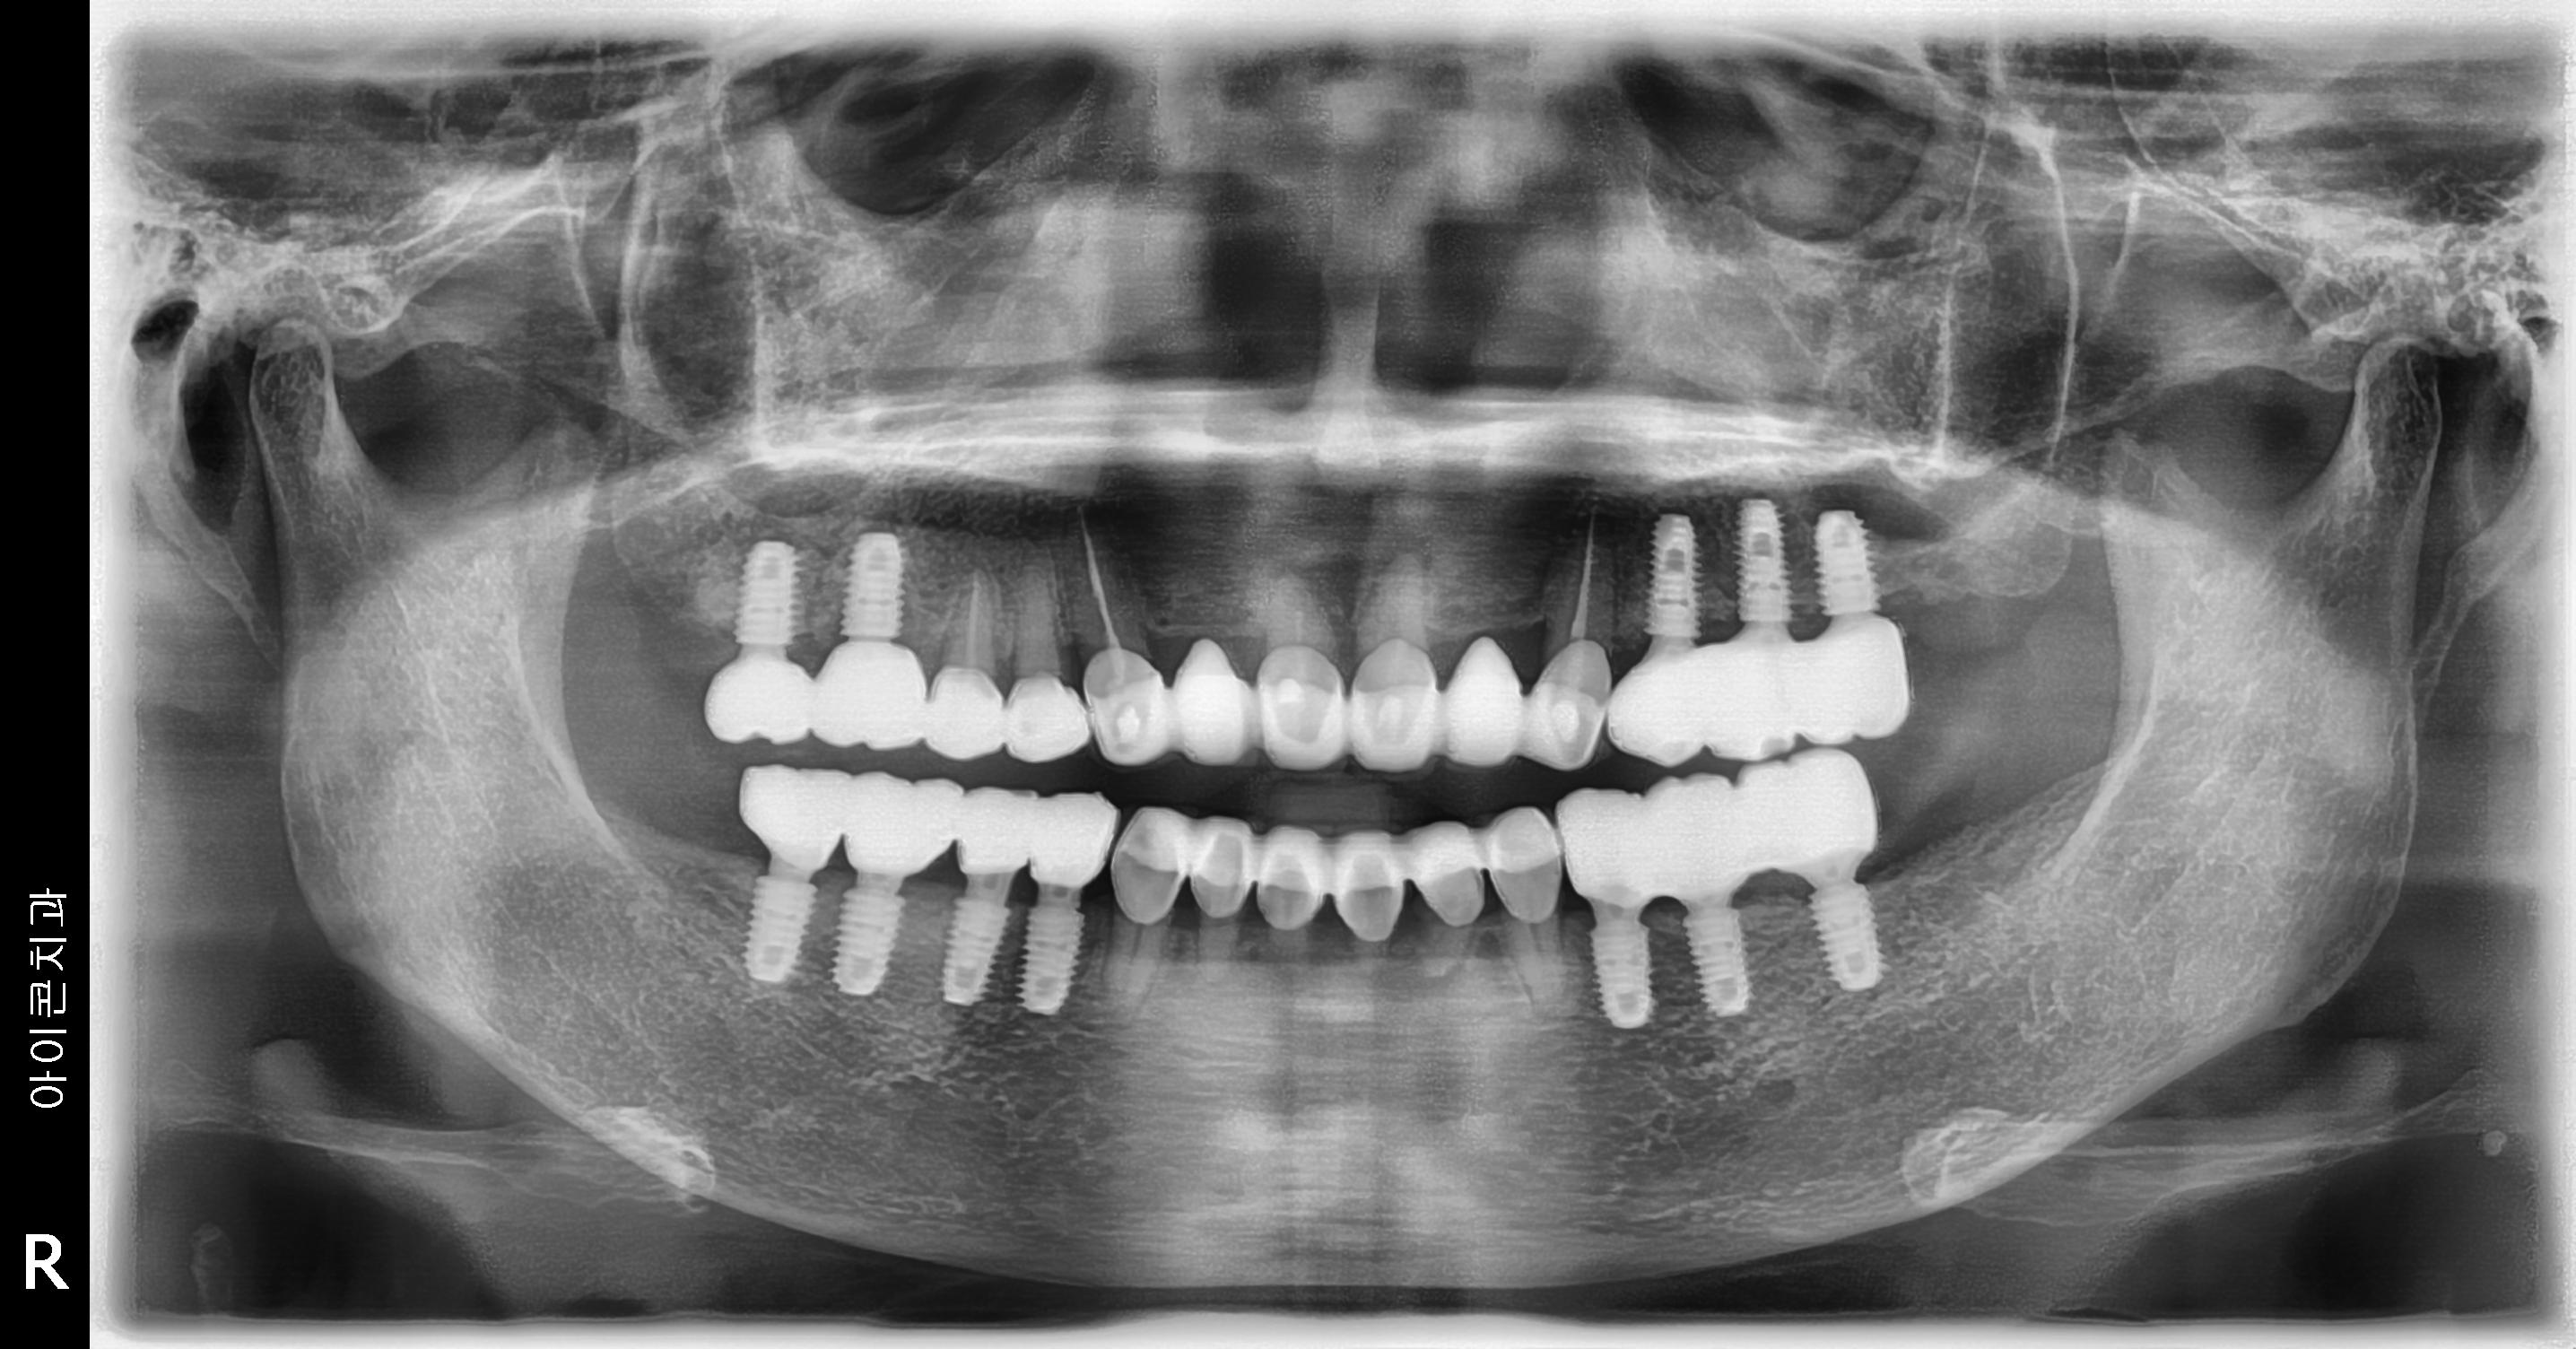

수술 전

수술 후

상하악 구치부 임플란트 식립사례

전후사진

하악 임플란트 식립사례